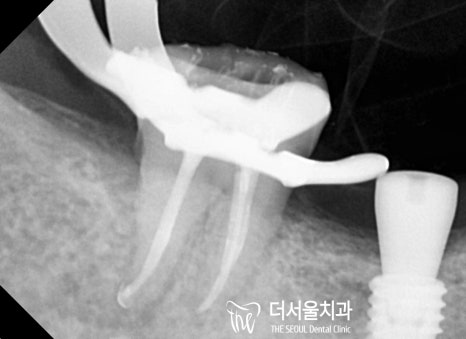

더 서울에서 정확한 진단을 위해

엑스레이 촬영을 진행한 결과,

하악 우측 잔존 어금니는 심한 충치로 인해

병소가 치수까지 감염되어 있었습니다.

자, 이제는 썩은 치아 곳을 진료해 드릴 차례입니다.

감염된 곳에 작은 홀을 뚫어

치수로 접근할 수 있는 통로를 만들어 주었습니다.